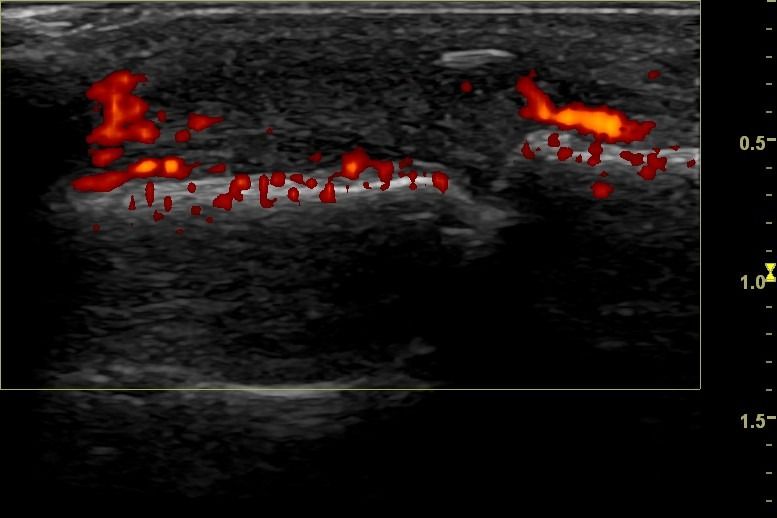

Rheumatic Diseases

- Rheumatoid Arthritis

- Psoriatic Arthritis

Dynamic Testing: Hand Ultrasound allows assessment of hand movement dynamically. This is particularly important for evaluating conditions affecting the range of movement, such as tendonitis and joint injuries.